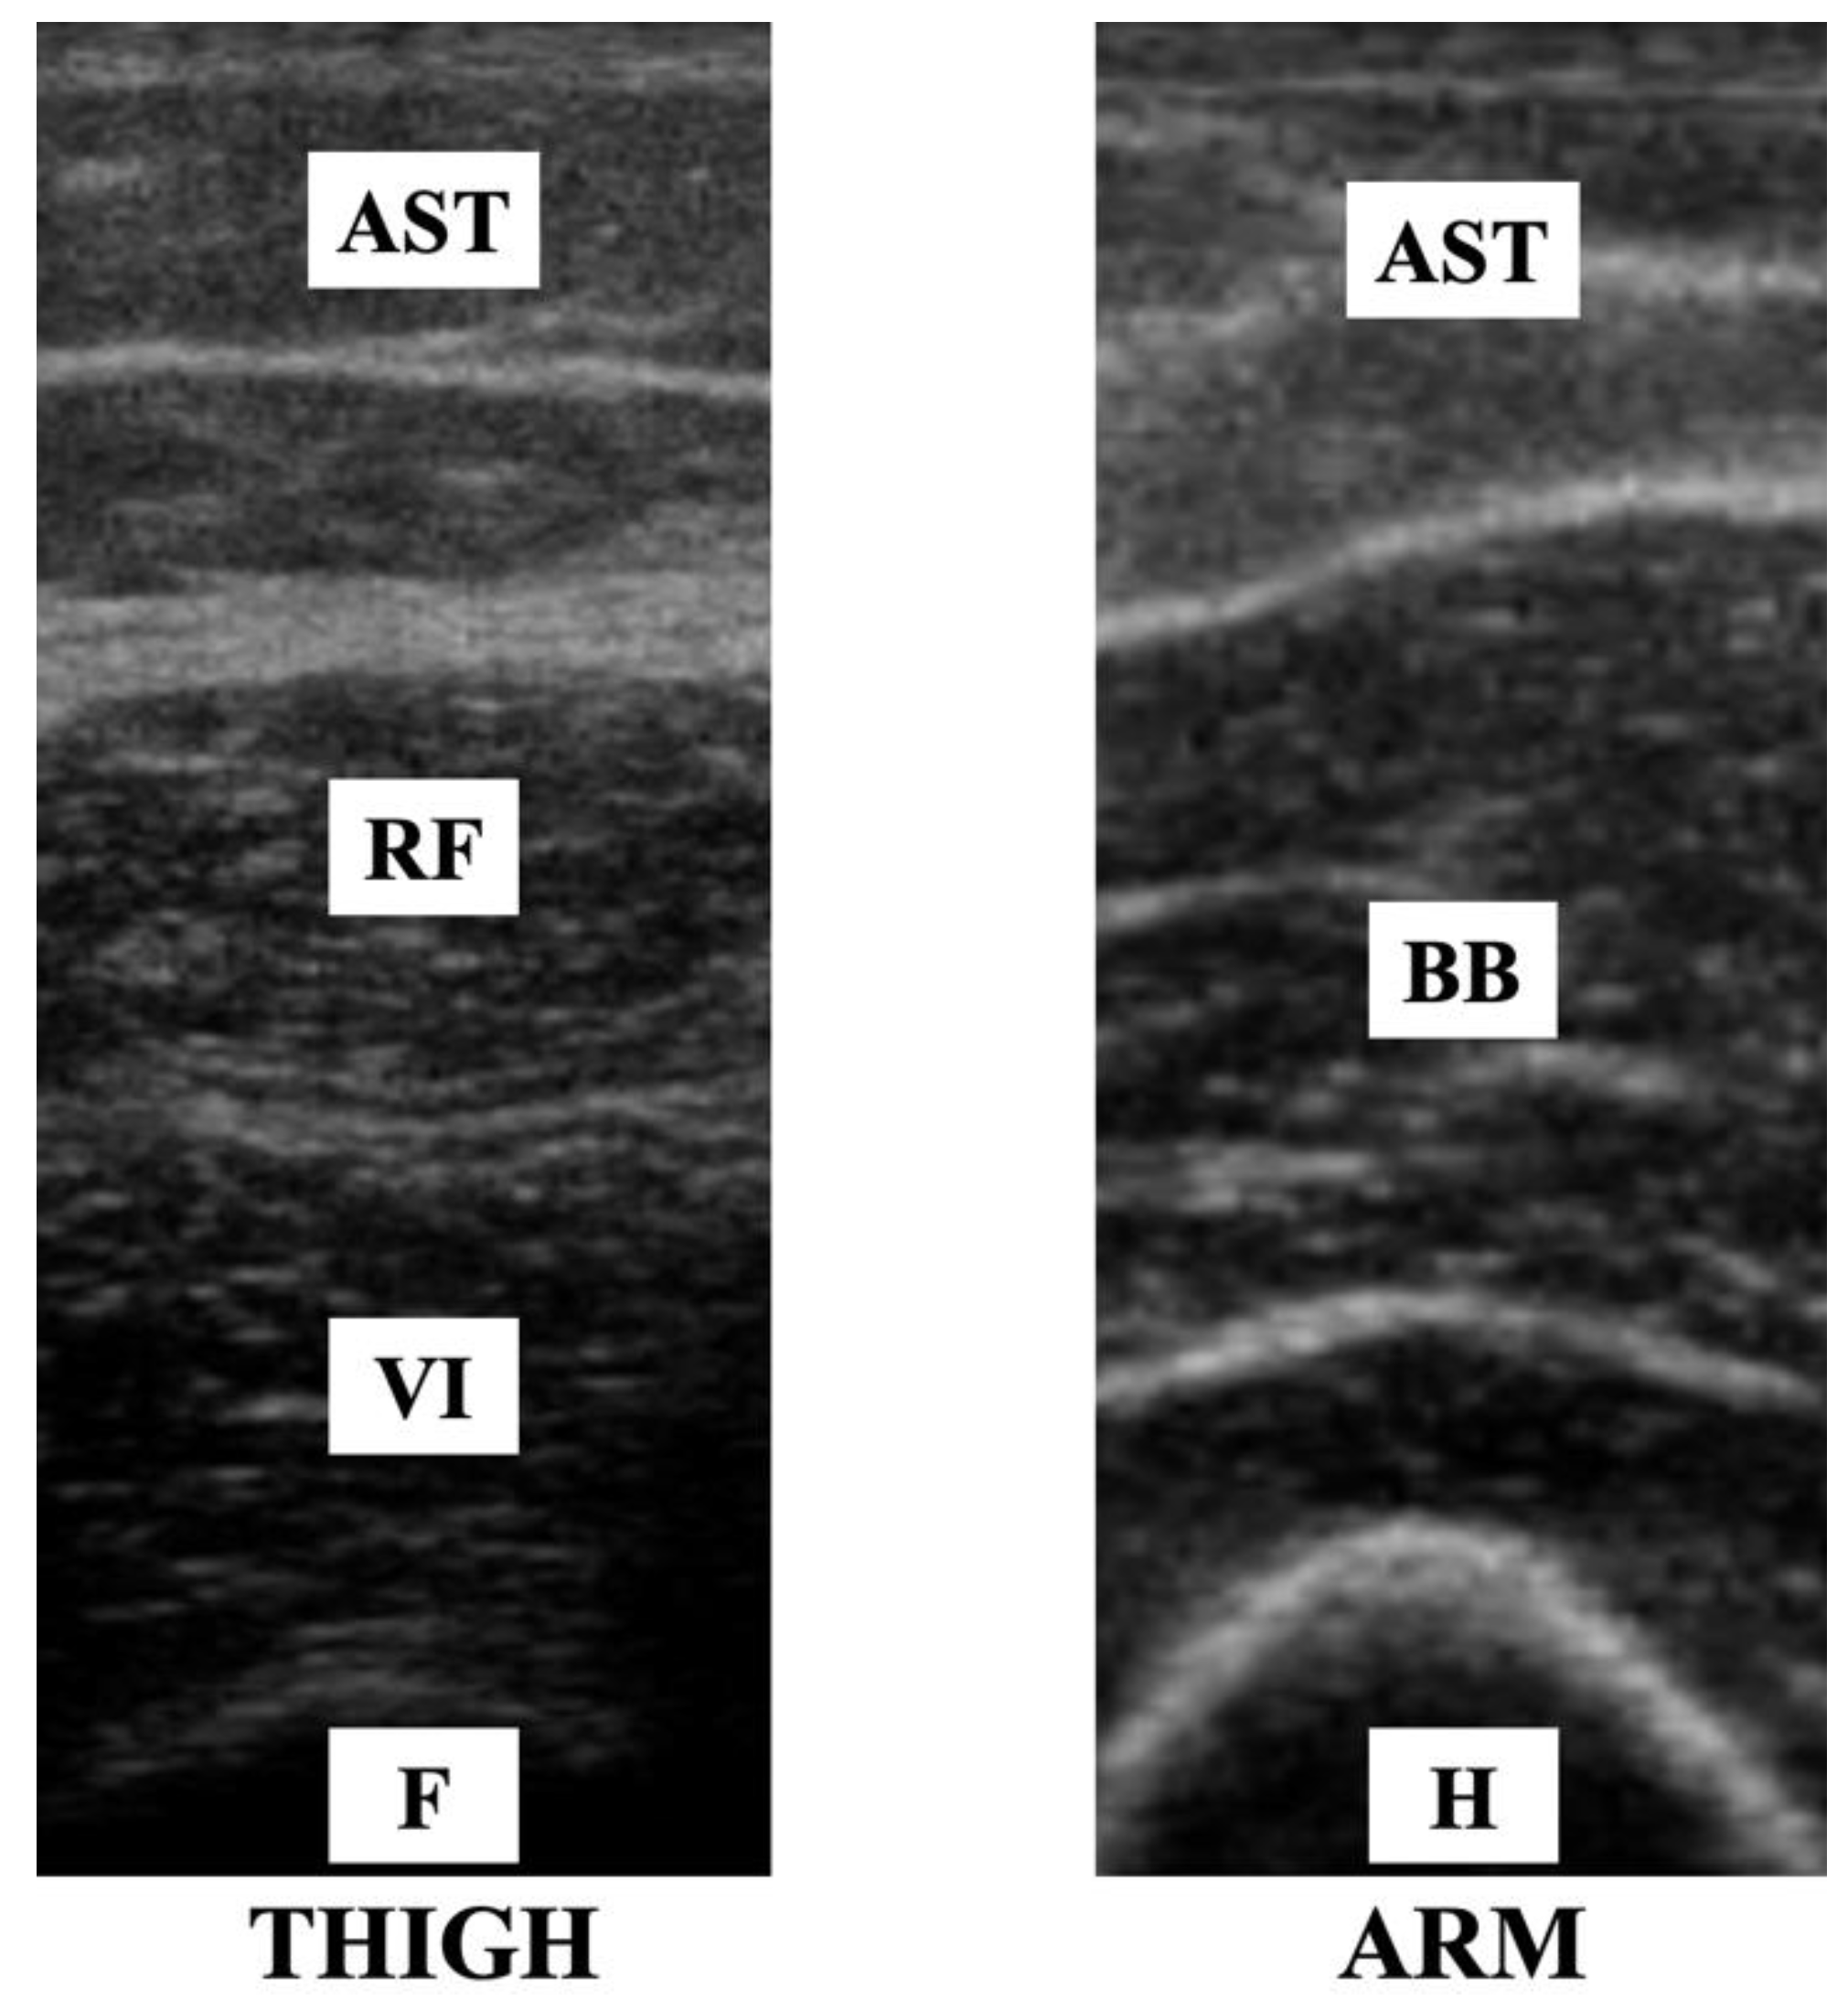

2.4. Muscle Thickness and Echo Intensity